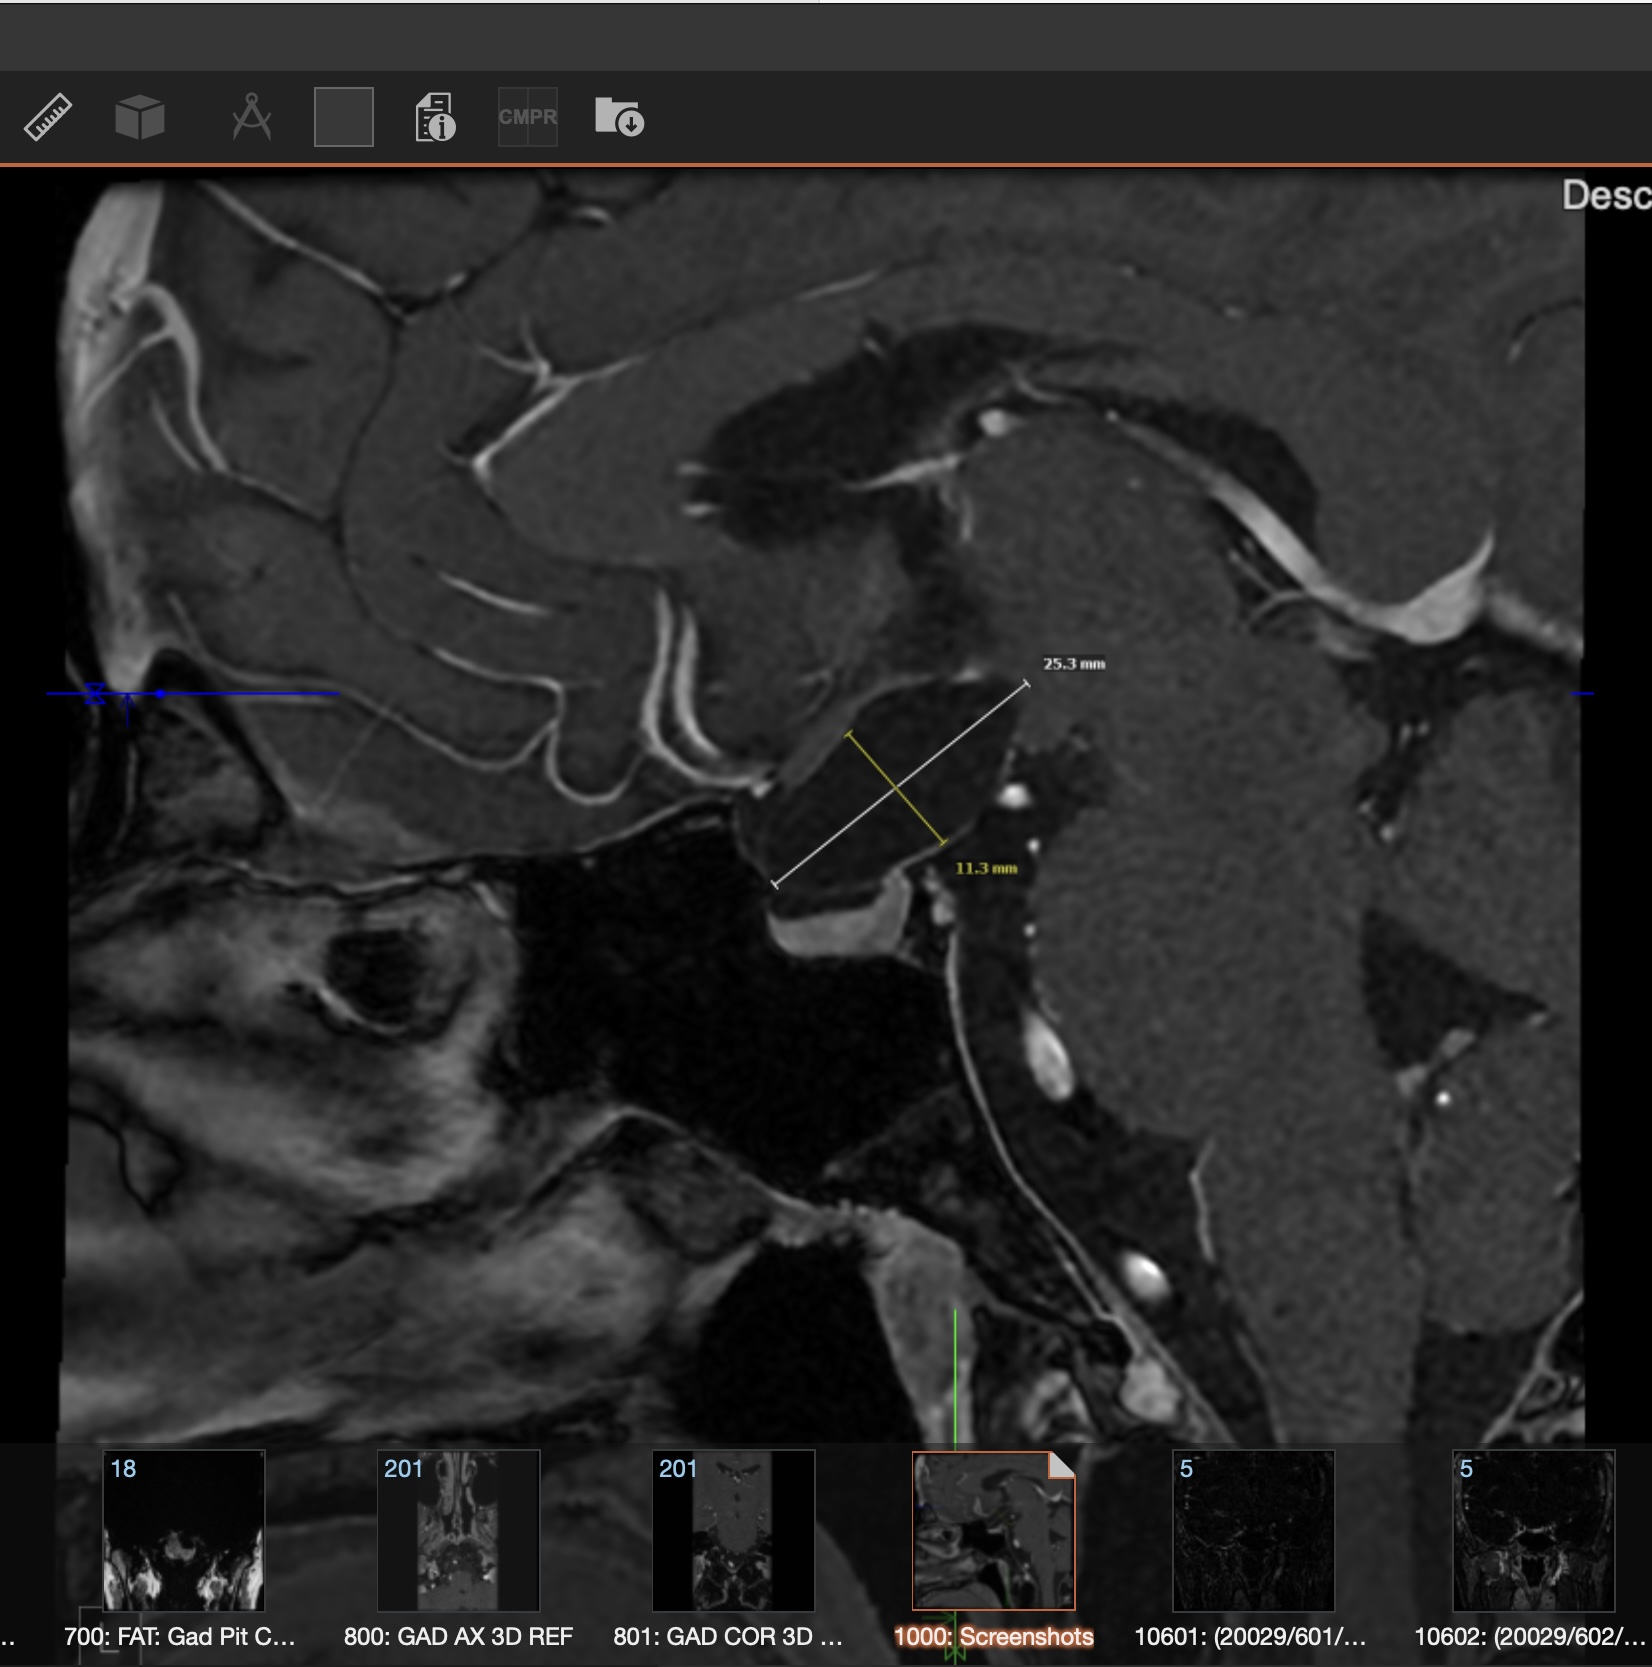

So now I get brain MRIs every 6 weeks, which is intense — but the tumor has a history of growing really fast, so it also keeps me safe. The biggest concern is that if it grows, more damage could be done to my pituitary stalk, optic chiasm, and hypothalamus (these are very important parts of the brain, if you didn't know — they refer to this area as the prime real estate of the brain). I am a very rare unicorn in that my Hypothalamic-Pituitary Axis has no deficiencies after two brain surgeries and two recurrences — even after the first tumor, at 4cm, put extreme strain on it. I am actually being screened again by my new endocrinologist because it's literally unheard of. Looking back, I can see that God definitely had a hand in this miracle. The original misdiagnosis was actually a blessing, because the brain surgeries I had did not harm the most critical part of my brain. My connection with a higher power has definitely brought me through the darkest of times and made my faith stronger. That's the strange and unexpected thing about serious, life-threatening disease — you are forced to go on a spiritual journey, and the way you live, see things, and feel things will forever be different. I'll be honest: I am still in shock that after three years of fighting, I am here and I am okay. Doctors and people look at me and cannot believe I seem and look normal after reading my medical chart. That is my miracle — it still brings me to tears with gratitude. I am not fearful of going through more hardship; I am only annoyed at the thought of having to go back into the process of it — the restriction, the endless blood draws, the weeks filled with appointments, feeling sick, picked, probed, and prodded. Feeling like more of a lab rat than a person, and feeling like my body isn't mine anymore. But I am taking my body back these past couple of weeks and slowly getting physically stronger. Slowly learning to love myself and my body again. I am mentally stronger now than ever, and I know I will always be okay regardless of what comes my way.